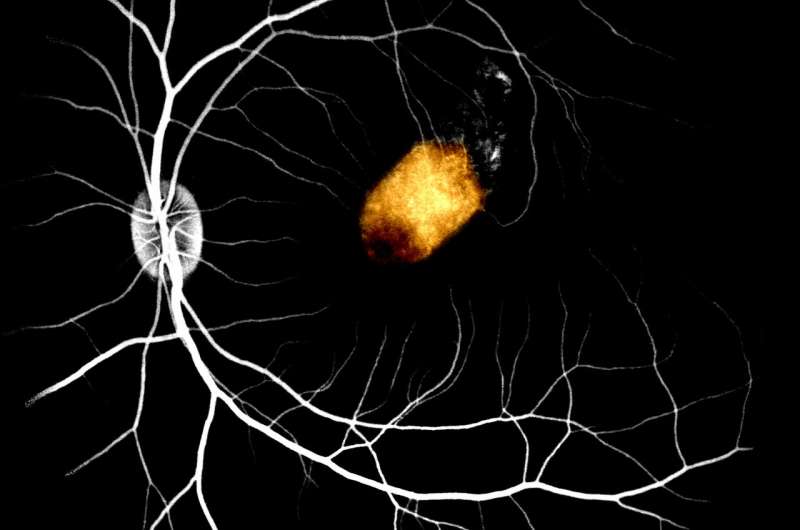

هذه صورة لزرع ال RPE مدرجة في المنطقة تحت الشبكية لنموذج الثديات غير البشرية

وجدت الدراسة أن رقاع batches ال RPE المزروعة تحت البقعة الشبكية[2] ، وهي الجزء المركزي من الشبكية، ظلت مستقرة ومتكاملة في الجسم الحي لمدة ثلاثة أشهر على الأقل دون آثار جانبية خطيرة كالهجوم المناعي [وهو ما يحدث حينما يهاجم الجهاز المناعي أعضاء وأجزاء داخلية في الجسم بشكل خاطئ، انظر[4] و[3] » والحساسية للضوء. وجد الباحثون أيضًا أن ال RPE المشتقة من الخلايا الجذعية اضطلعت بوظيفة ال RPE الأصلية جزئيًا على الأقل وكانت قادرة على دعم مستقبلات الضوء الداخلية الأصلية endogenous، مما يساعد في امتصاص الضوء والماء من بين وظائف أخرى.